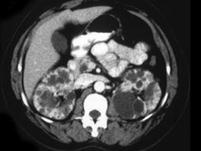

问题 女,35岁,无特殊临床表现,请根据CT图像,选择最可能诊断 ( )

选项 A、囊性肾癌 B、单纯性肾囊肿 C、多发性肾囊肿 D、复杂性肾囊肿 E、多囊肾

答案 E